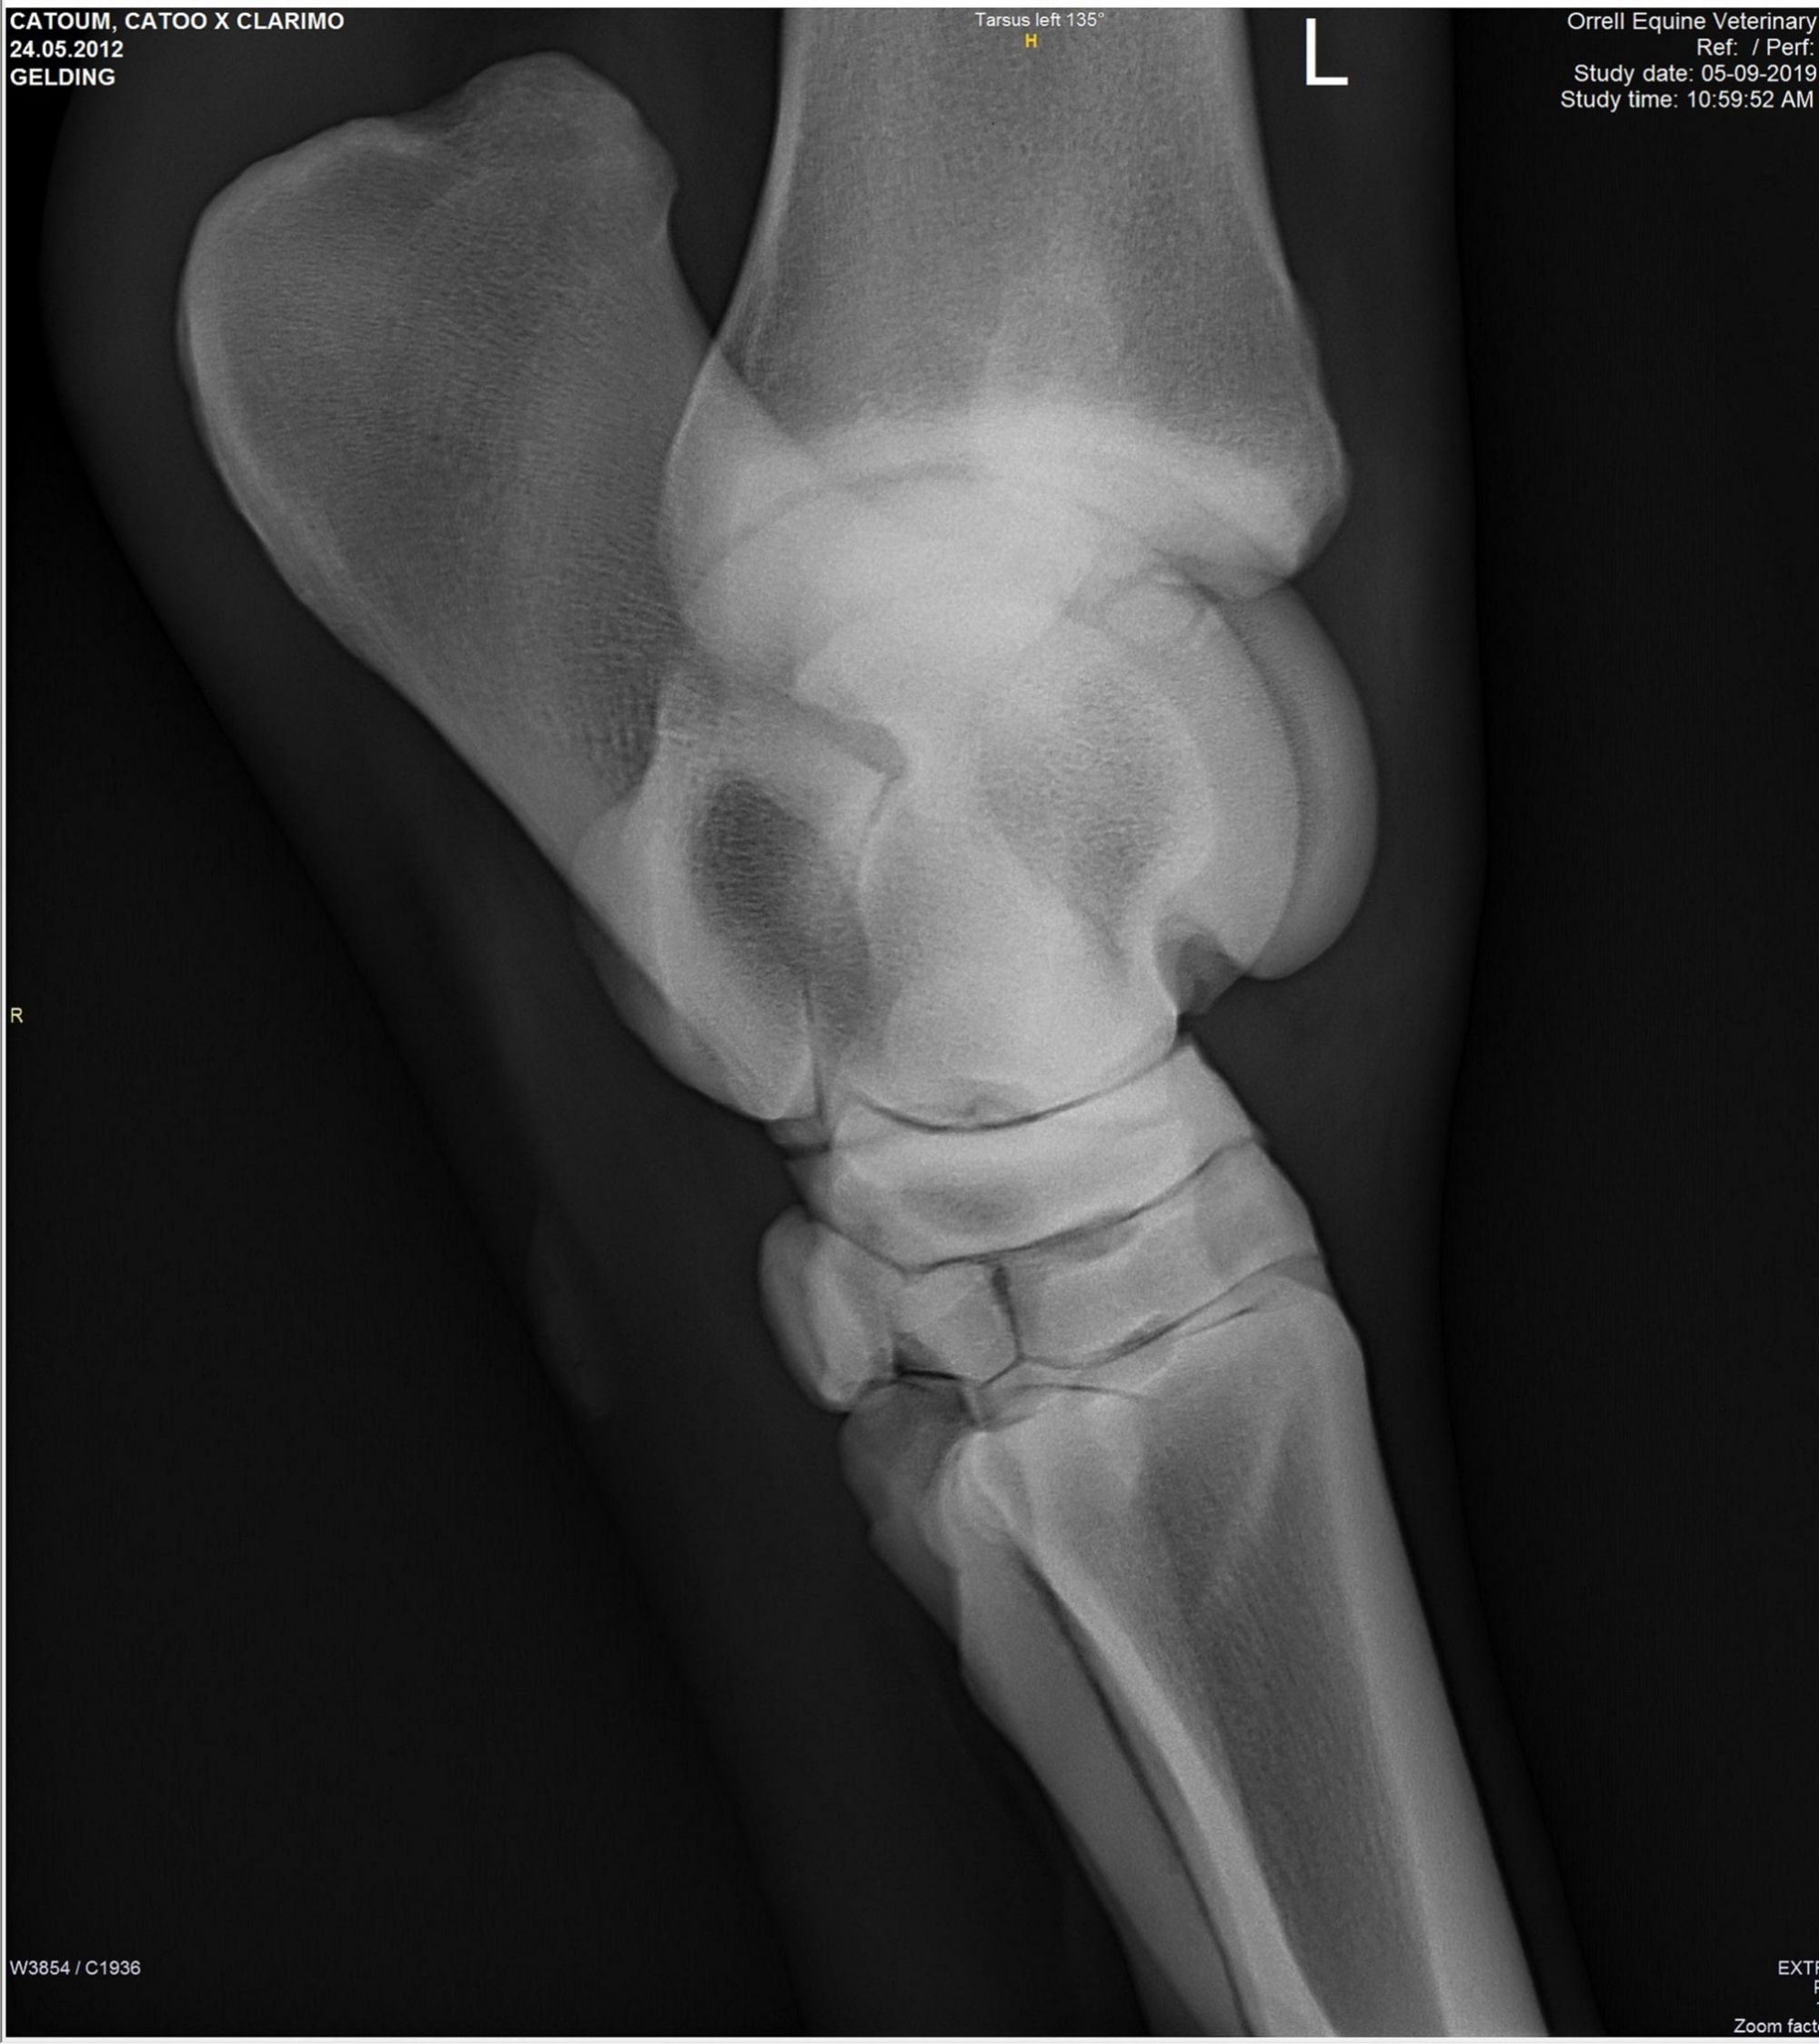

Snart dök det även upp röntgenplåtar, utan att Marina ens hade frågat efter dem. Röntgenbilderna skickade Marina vidare till två olika veterinärer för bedömning. Bägge såg lösa benbitar i ena hasen och Cecilia Grahn på Kungsbacka Hästklinik hade en mejlkonversation med den engelske veterinären ”Steve Orrell” som hade tagit bilderna. Att bilderna var falska och att det inte var den riktige Steve Orrell var det ingen som visste då. Han skrev att han hade sett hästen sedan den var tre år och argumenterade först emot de tre lösa benbitar som Cecilia Grahn hade hittat.

Lucas Bailey skickar bilder på röntgenplåtar. Marina Johansson låter två olika veterinärer bedöma bilderna. Bägge såg lösa benbitar i ena hasen och Cecilia Grahn på Kungsbacka Hästklinik hade en mejlkonversation med den engelske veterinären ”Steve Orrell” som hade tagit bilderna. ”Veterinären” skriver att han har sett hästen sedan den var tre år och argumenterar för att benbitarna saknar betydelse.